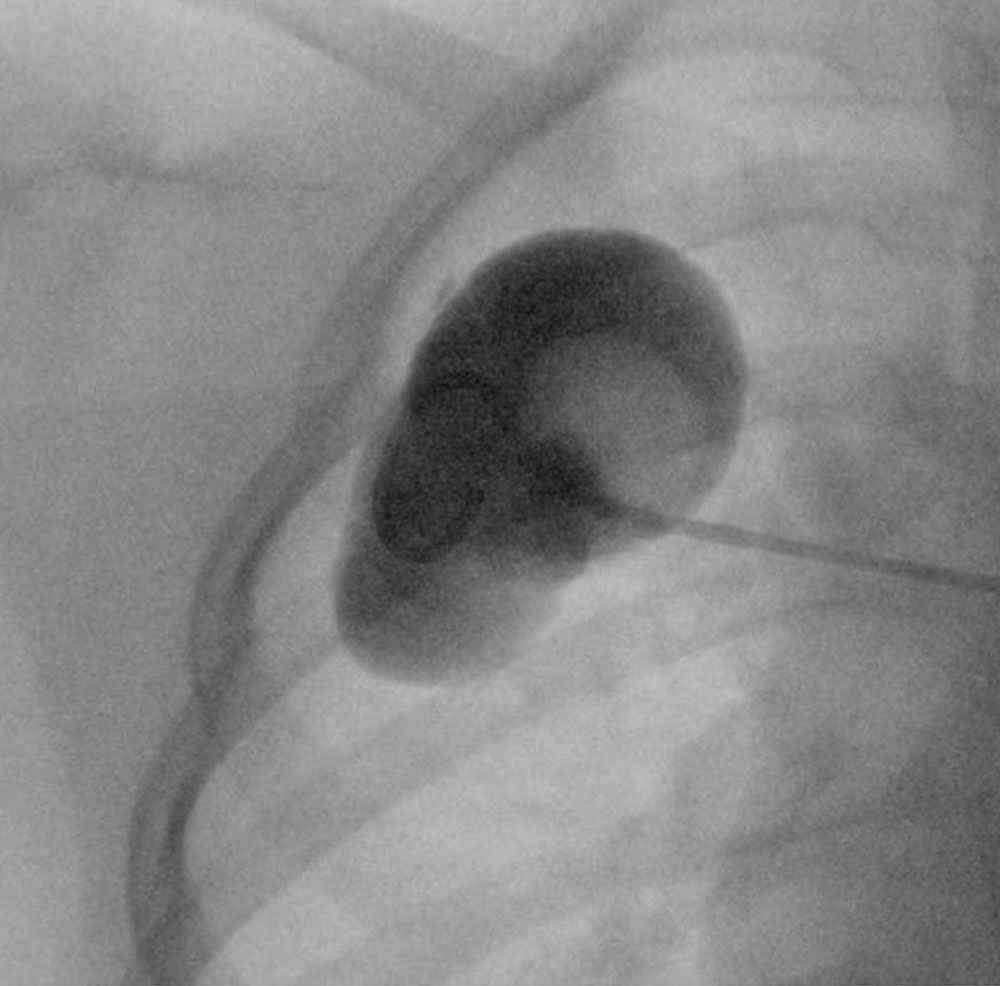

During sclerotherapy, to determine the volume and extension of a punctured LM and to exclude lymphovenous anastomoses, direct radiography (usually as fluoroscopy) of the punctured lymphocysts can be performed before the sclerosant is injected.